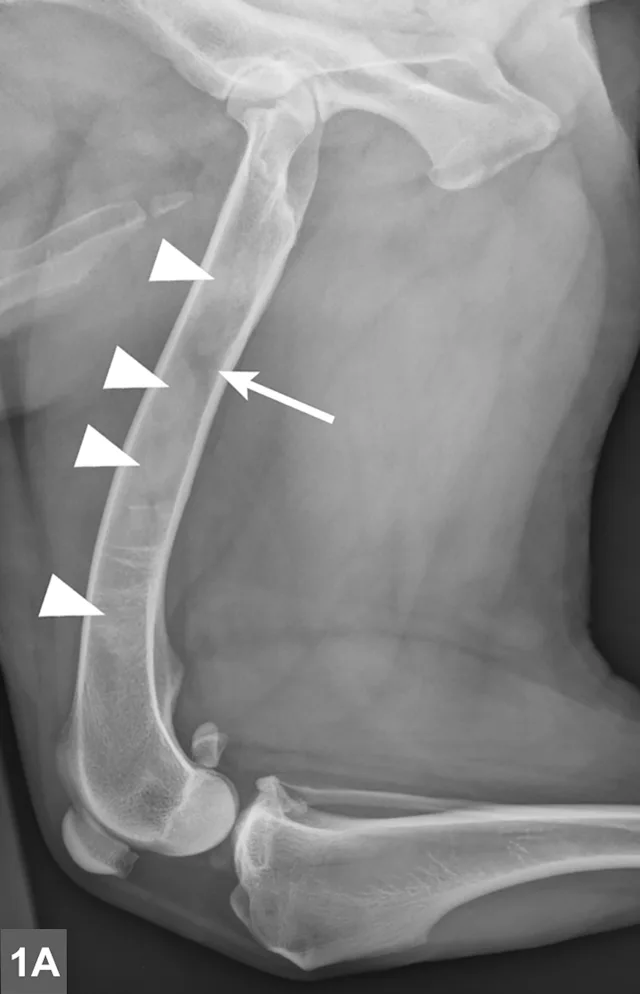

FIGURE 1A

Lateral radiographic projections of the femur (A) and ulna (B, next slide) in dogs with early signs of panosteitis. Note the radiolucency around the nutrient foramen (arrows) and increased opacity within the medullary canal (arrowheads) in both cases.

Radiographic signs of panosteitis frequently lag days to weeks behind clinical signs.1,3 The earliest radiographic sign of panosteitis is a decrease in opacity around the nutrient foramen. Later signs include an increase in mineral opacity within the medullary canal of long bones and loss of the normal trabecular bone pattern (Figure 1). Smooth periosteal and endosteal new bone may also be seen in more severe cases (Figure 2). Radiographs of the affected limb may be compared with those of the contralateral limb to assist in diagnosis. Nuclear scintigraphy may assist in diagnosis in cases in which radiographic changes have not yet developed.4